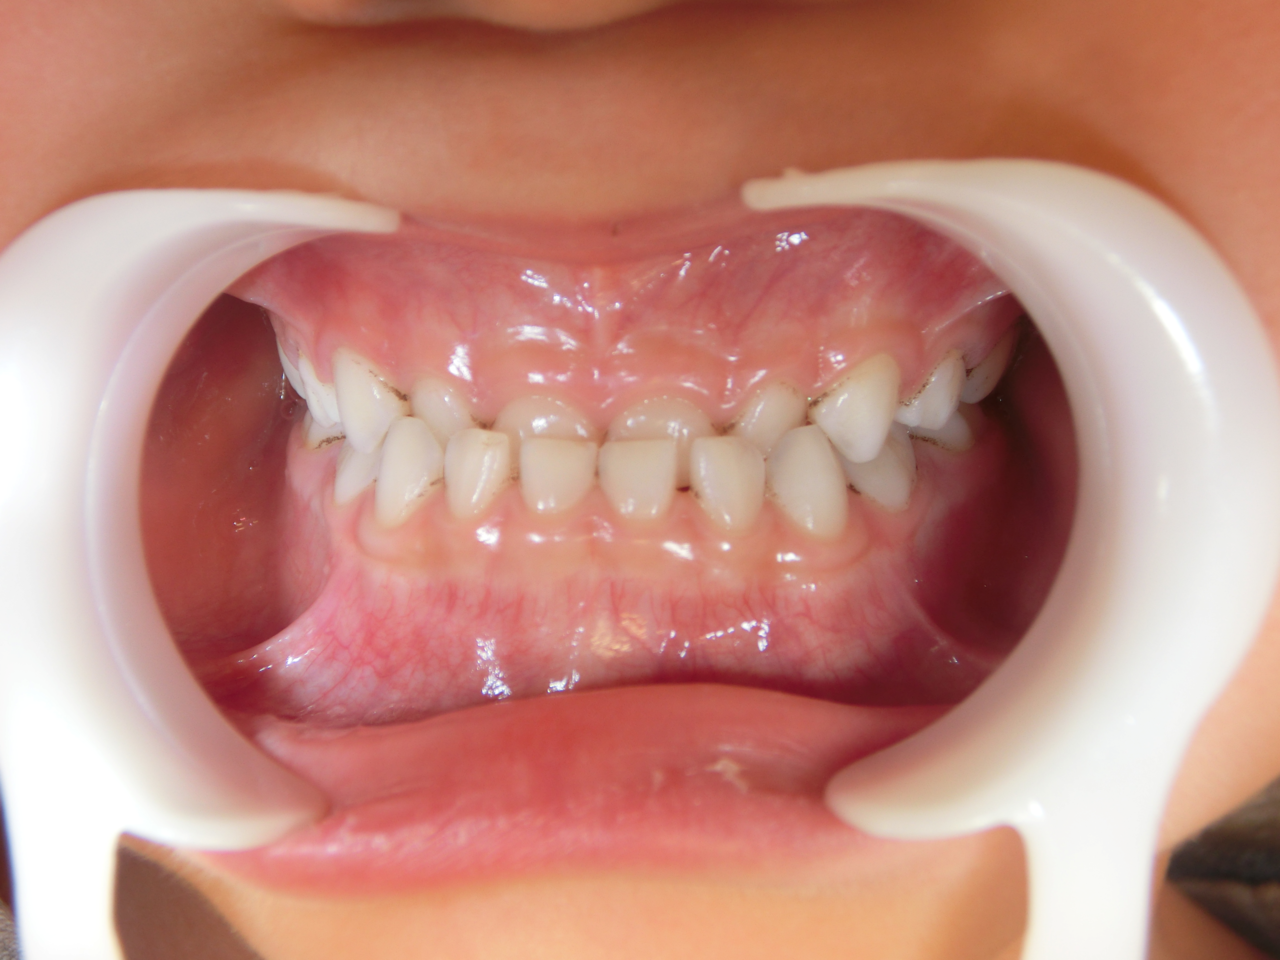

治療後

治療説明 歯科矯正で取り外し可能な矯正方法である床矯正で治療しました

治療期間 4年

治療費用200000 円

治療の副作用(リスク)歯の動き方には個人差があり、予想された治療期間が延長する可能性があります。。床矯正の使用状況、矯正歯科治療には患者さんの協力が必要であり、それらが治療結果や治療期間に影響します。2次矯正が必要になる場合もあります。